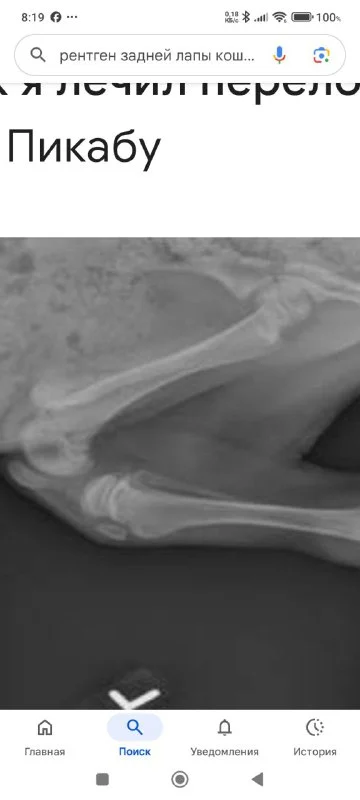

Доброе утро. Вопрос к знатокам. Вчера подобрала котенка со сломанной лапой. Отвезла в Small animals . Там сделали рентген, оказалось кость в двух местах из сустава выбита,плюс осколок. Я не сообразила сфотографировать. Сейчас приложу похожий снимок из интернета. Понять такое вообще лечится или только ампутация? У котенка пошел абсцесс. Вскрыли и выкачали целый стакан гноя. Сказали стабилизировать надо пару дней, а то наркоз не выдержит. Сегодня жду приговор